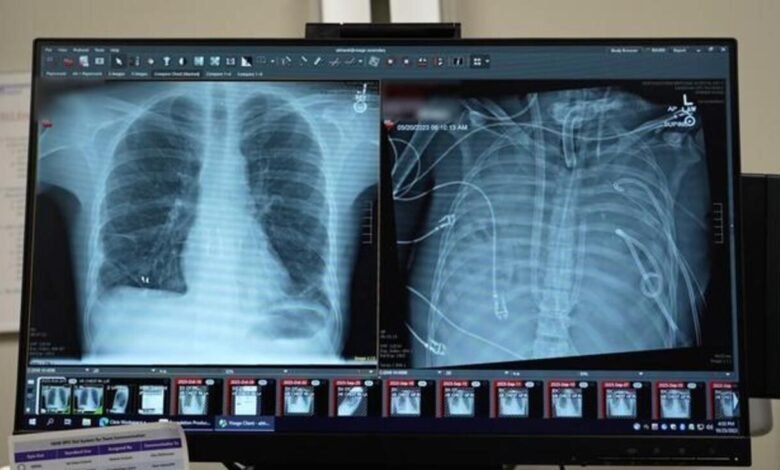

Un paciente de 33 años sobrevivió dos días sin pulmones mientras esperaba un trasplante doble en un hospital de Estados Unidos. El procedimiento, publicado en la revista Med, marcó un hito en la cirugía torácica y en el tratamiento de cuadros respiratorios agudos irreversibles.

Un equipo del Northwestern University Hospital, liderado por el cirujano torácico Ankit Bharat, extrajo ambos pulmones infectados de un joven con síndrome de dificultad respiratoria aguda (ARDS) para frenar una infección que avanzaba rápidamente y comprometía otros órganos. Durante 48 horas, el paciente permaneció con un sistema extracorpóreo que oxigenaba su sangre y reemplazaba de manera temporal la función pulmonar hasta que aparecieron órganos compatibles. El caso fue cubierto por medios especializados y portales de ciencias como Robotitus.

El hombre ingresó en estado crítico tras una gripe que derivó en una neumonía bacteriana severa. La inflamación destruyó prácticamente sus pulmones y desencadenó fallas cardíacas y renales.

Al analizar los pulmones extraídos, los especialistas confirmaron que el daño era irreversible: cicatrices extensas y lesiones inmunológicas que hacían imposible cualquier recuperación espontánea.